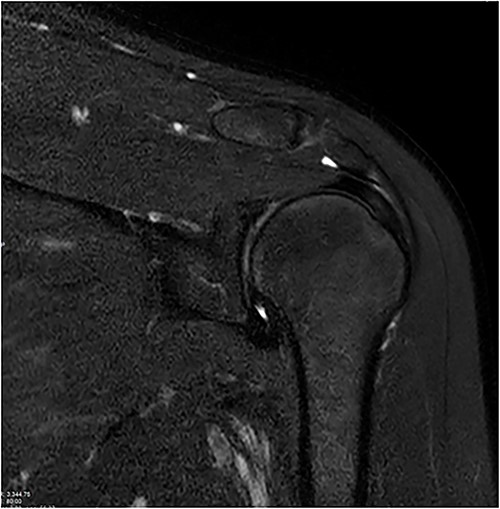

Coronal and axial T2 fat saturated image of left shoulder showing thickened inferior capsule of low T2 signal, characteristic of freezing phase in adhesive capsulitis.

Coronal and axial T2 fat saturated image of left shoulder showing thickened inferior capsule of low T2 signal, characteristic of the freezing phase in adhesive capsulitis.